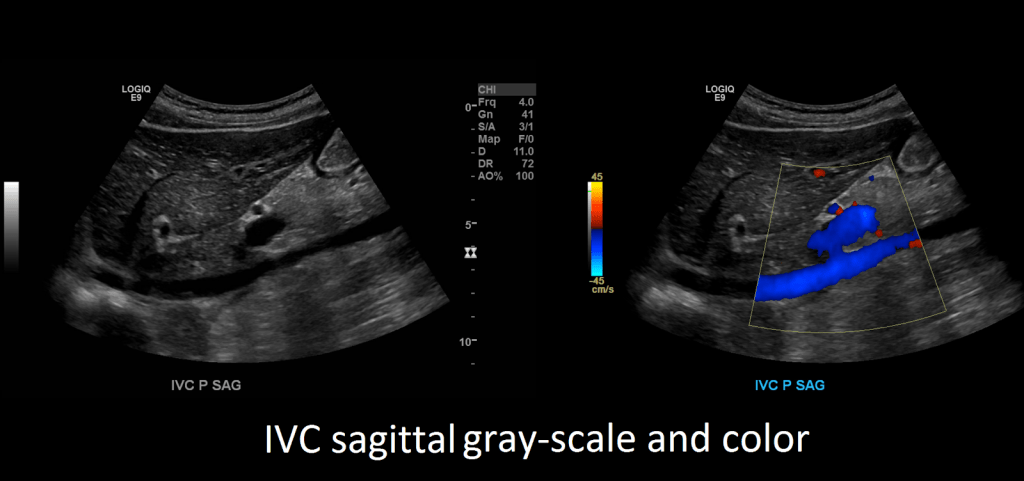

After you’re done evaluating the aorta, turn your attention to the inferior vena cava. Capture images in sagittal and transverse in grayscale, color and spectral Doppler.